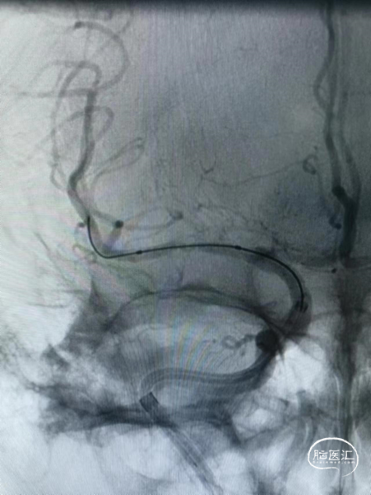

支架通过病变。

支架释放。